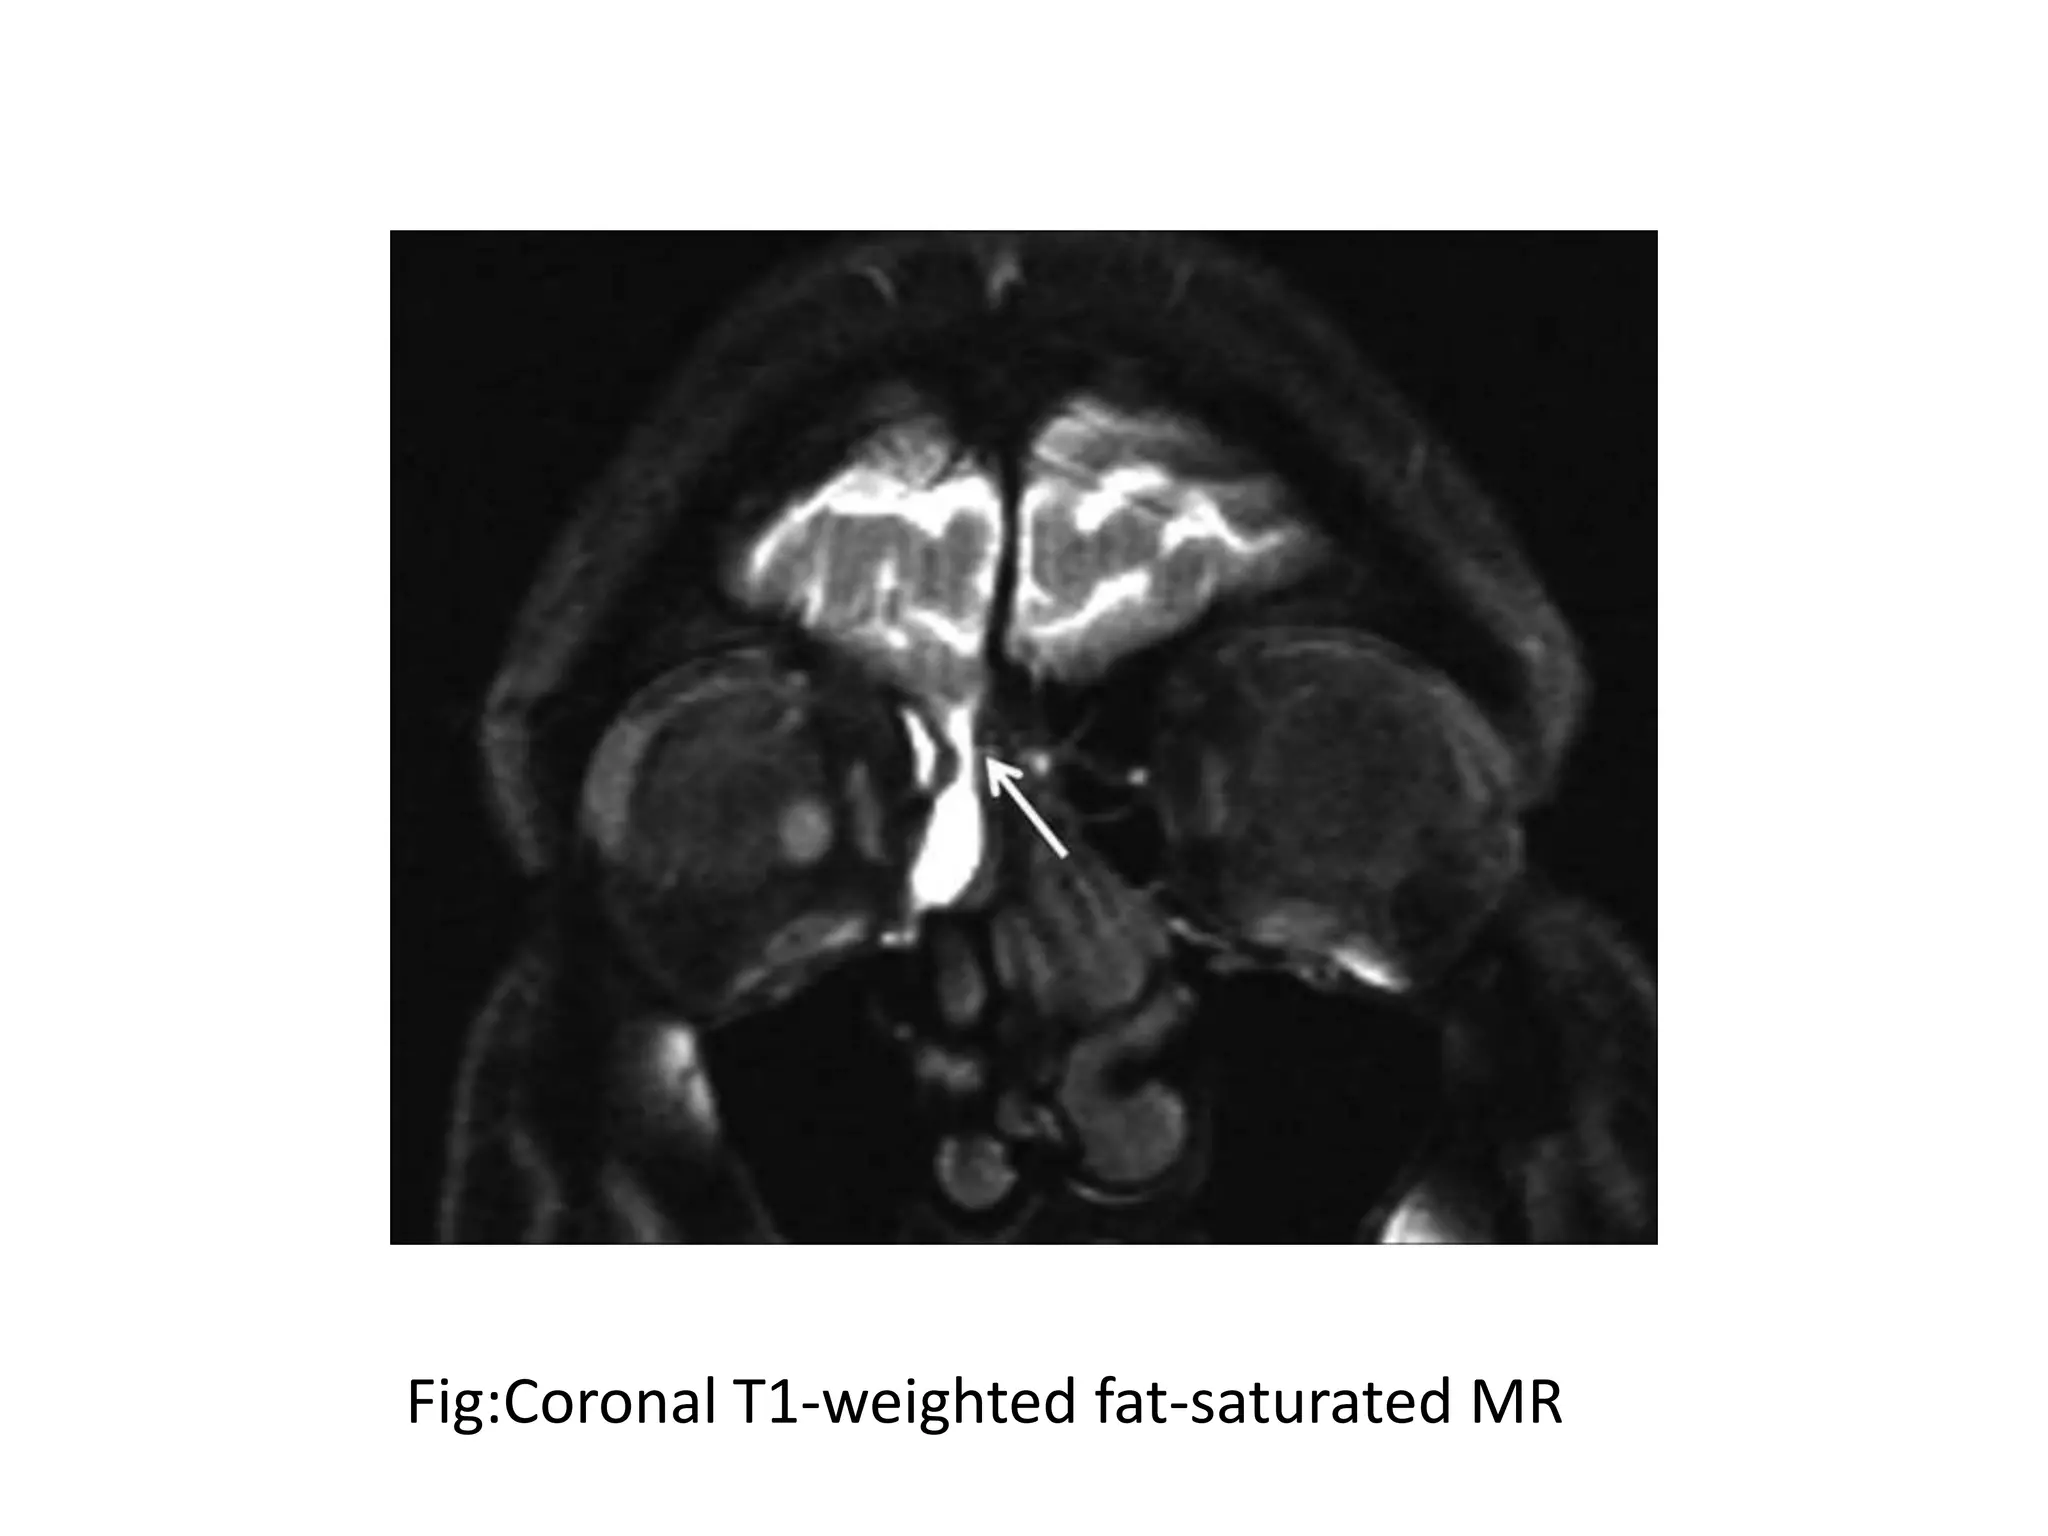

• Gd-enhanced MR cisternography (Gd-MRC) to confirm and

• One hour after injection, the patient was moved

into a prone position and fat-saturated T1-

weighted images were obtained in 3 orthogonal

planes.

• Coronal and sagittal T1-weighted images (TR/TE,

500/17 ms; 2 signals acquired) and axial T1-

weighted images (TR/TE, 600/17 ms; 2 signals

acquired) were obtained by using a 1.5T MR

imaging unit

Fig:Coronal T1-weighted fat-saturated MR

FIG:Sagittal T1-weighted fat-suppressed MR image